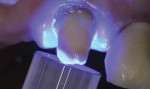

Isolation was obtained by placing a cotton roll in the labial vestibule. A portion of the crown margin was obstructed by a piece of gingival tissue; therefore, a retraction cord was placed to allow complete access to the margin. For this case, the authors chose a universal bonding agent (All-Bond Universal®, Bisco, Inc.), which can be used in a total-etch, selective-etch, or self-etch mode; they used a self-etch method. Some self-etch adhesives require a dual-cure activator to be mixed with the adhesive prior to use with a dual-curing cement. The universal adhesive used here, however, does not require a dual-cure activator. The preparations received two coats of adhesive and were scrubbed for 15 seconds (Figure 9). The adhesive was then air-dried for 15 seconds until there was no visible movement of the adhesive. Prior to light-curing the adhesive, the preparations were examined to confirm that there was no puddling of the adhesive, which would have prevented complete seating of the crowns. The adhesive was light-cured for 10 seconds (Figure 10). (Author’s note: The manufacturer’s instructions should be referenced to confirm that light-curing the adhesive is necessary, as some adhesive/cement combinations, such as Scotchbond™ Universal/RelyX™ Ultimate [3M ESPE, www.3MESPE.com], contain chemical initiators in the cement that polymerize the adhesive.)